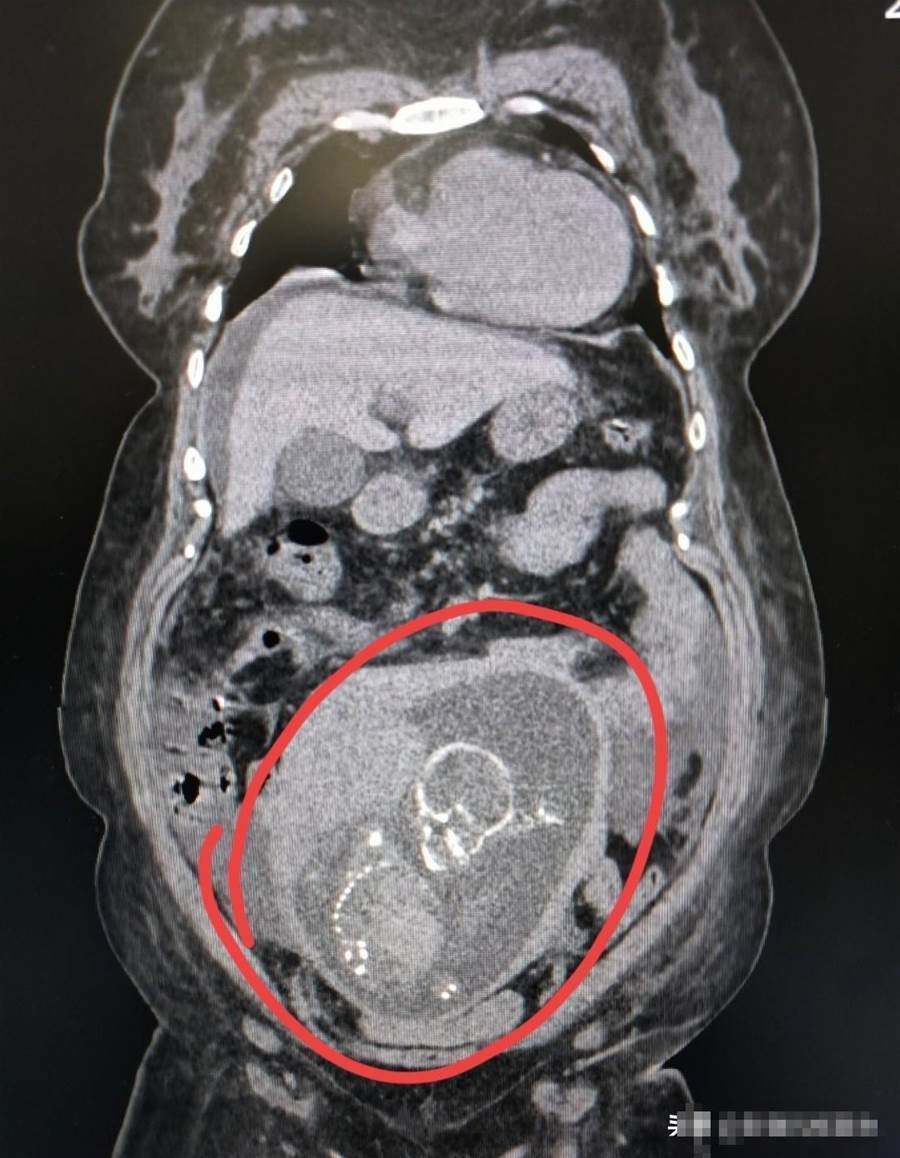

技師按常規流程為王女士擺好體位,開始掃描。監視器的影像一出現,操作間裡的人都怔住了——盆腔區域清晰地顯示出一個已經成形的胎兒頭顱。技師下意識脫口問道:「您懷孕了?怎麼還來做CT?」話音剛落,李先生的臉「唰」地沒了血色,猛地抓住技師的手臂:「什麼懷孕?你們是不是弄錯了?」